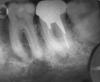

Зубная фея79 Опубликовано 30 октября, 2010 Поделиться Опубликовано 30 октября, 2010 Нижняя семерка, стоит вкладка серебро и металлокерамика 4 года, депульпирован 4 года назад. Болит при надкусывании, день сильно, потом не очень,можно есть... Прикладываю снимок, скажите, можно спасти как-то этот зуб? Ссылка на комментарий

x3m Опубликовано 30 октября, 2010 Поделиться Опубликовано 30 октября, 2010 Нижняя семерка...можно спасти как-то этот зуб?думаю, можно.надо снять коронку.если зуб не сильно разрушен - аккуратно убрать штифт и, если корень не перфорирован - перелечить каналы.т.е. распломбировать их, хорошенько промыть антисептиками и плотно запломбировать до верхушек корней.затем - восстановить штифтом (ВКВ) и изготовить коронку на этот зуб. При невозможности такого плана - удалить и поставить имплантат (идеальный вариант). Ссылка на комментарий

Зубная фея79 Опубликовано 31 октября, 2010 Автор Поделиться Опубликовано 31 октября, 2010 На зубе стоит серебряная вкладка и металлокерамика. И пристутствует воспаление на корне. Я хочу узнать, возможно ли снятие вкладки или гемисекция? Ссылка на комментарий

x3m Опубликовано 31 октября, 2010 Поделиться Опубликовано 31 октября, 2010 На зубе стоит серебряная вкладка и металлокерамика. И пристутствует воспаление на корне. Я хочу узнать, возможно ли снятие вкладки или гемисекция?я понял исходную ситуацию.прочтите мой пост еще раз.гемисекция к этому случаю не имеет никакого отношения. Ссылка на комментарий

Voldemar Опубликовано 31 октября, 2010 Поделиться Опубликовано 31 октября, 2010 На зубе стоит серебряная вкладка и металлокерамика. И пристутствует воспаление на корне. Я хочу узнать, возможно ли снятие вкладки или гемисекция?Не понятно, почему так много вопросов на этом форуме, по поводу такой сомнительной (во всех аспектах) операции- как Гемисекция! Зачем Вам пол зуба- если есть целый! Или зачем Вам пол зуба- если он не целый! Но в Вашем случае, гемисекция затруднительна, из-зя топографии верхушек корней 7-го зуба! Ссылка на комментарий